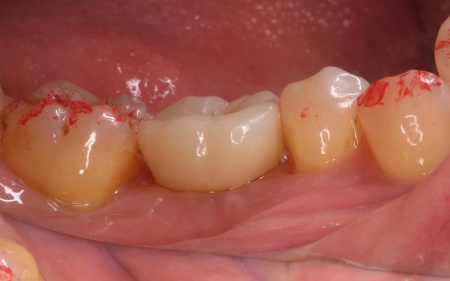

治療後